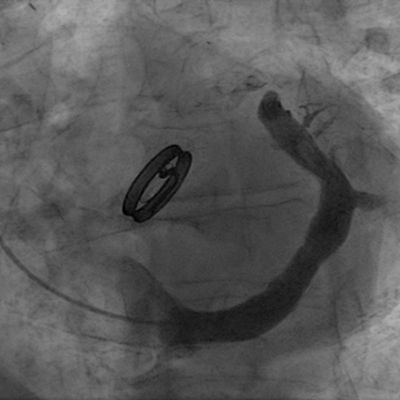

"Coronary sinus narrowing for the treatment of refractory angina A multi-center prospective open-label clinical study (The REDUCER-I study)" by Stefan Verheye et al. #EAPCI bit.ly/3gR4kPm

"Coronary sinus narrowing for the treatment of refractory angina A multi-center prospective open-label clinical study (The REDUCER-I study)" by Stefan Verheye et al. #EAPCI

Coronary Sinus Reducer to Improve Angina: -n=15 -greater ischemia improvement with smaller CS sizes -suggests mechanism of Reducer non-responsiveness in 15-30% of pts onlinelibrary.wiley.com/doi/full/10.10… Follow @CCIJournal, facebook.com/CCIJournal Official Journal of SCAI

Coronary Sinus Reducer to Improve Angina:

-n=15

-greater ischemia improvement with smaller CS sizes

-suggests mechanism of Reducer non-responsiveness in 15-30% of pts

Francesco Giannini presenting the results of First-in-human experience with a novel self-expandable coronary sinus reducer for treating symptomatic epicardial and microvascular ischemic heart disease at #TCT2025 Cardiovascular Research Foundation VahatiCor Jean-Michel Paradis #CardioX #CardioTwitter #CardioEd

<a href="/fra_giannini1/">Francesco Giannini</a> presenting the results of First-in-human experience with a novel self-expandable coronary sinus reducer for treating symptomatic epicardial and microvascular ischemic heart disease at #TCT2025 <a href="/crfheart/">Cardiovascular Research Foundation</a> <a href="/VahatiCor/">VahatiCor</a> <a href="/Jmparadis27/">Jean-Michel Paradis</a>